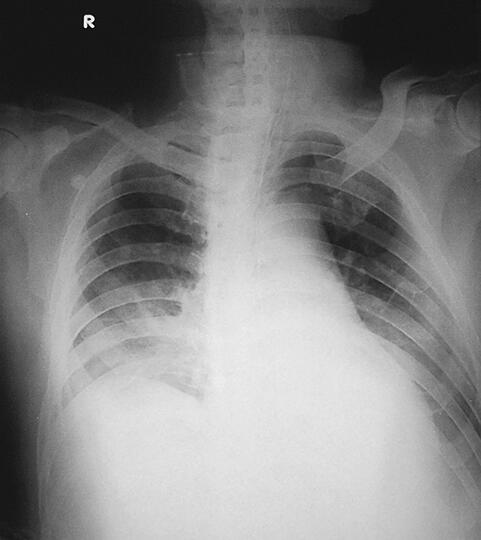

诊治经过:患者入笔者科室后一般情况较差,血压测不出,氧饱和度84%,予以羟乙基淀粉扩容,多巴胺、去甲肾上腺素微泵维持血压,碳酸氢钠纠正酸中毒。立即予以气管插管,呼吸机辅助通气。完善相关检查:CT(图1)结果:①头颅CT平扫未见明显异常;②双下肺肺不张;③双侧胸腔积液;④肝右叶钙化灶。血常规(2月7日):WBC 20.9×109/L,N 94%。心脏彩超(2月8日):左心室舒张末内径61mm,射血分数38%。胸片(图2~图4)诊断:①双侧肺炎;②颈椎术后。先后给予头孢曲松钠和左氧氟沙星、美罗培南和替考拉宁抗感染。因痰培养鲍曼不动杆菌(2月10日),对头孢哌酮-舒巴坦钠敏感,余均耐药,故停用美罗培南,改用头孢哌酮-舒巴坦钠。多次血培养结果提示白念珠菌(2月6日、2月7日、2月9日、2月10日),对氟康唑和伊曲康唑均敏感,因为患者肌酐高,肾功能异常,故给予米卡芬净和氟康唑抗真菌治疗。患者血糖高,2月6日末梢血血糖33.1mmol/L,给予胰岛素强化治疗,但是血糖控制不佳,一直在11mmol/L以上。同时给予化痰、抗炎、保肝、营养神经、调节机体免疫、加强营养、维持内环境稳定、对症支持等治疗。

图2 2月9日胸片